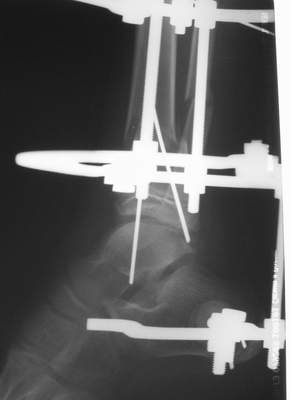

A> Это сросшийся перелом малоберцовой кости. И ложный сустав

A> н\3 б\берцовой кости.

Таперича это ясно.

А аппаратами пользуетесь?

Нашел в комп-ре схожий случай:

1) з/репозиция, 2) фиксация 2 спицами, 3) аппарат, 4) фиксационные

спицы удалены...

См. аттачт.

А можно было наложить аппарат и по поводу ложного сустава...

По крайней мере не было бы укорочения (пусть и в 2 см)...